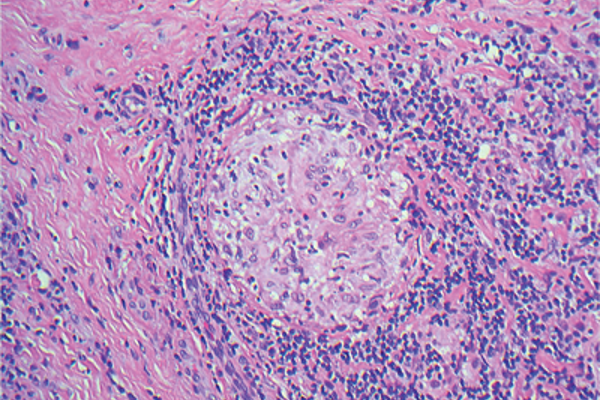

Pathology Quiz - Section Editor until Aug/Sep 2016